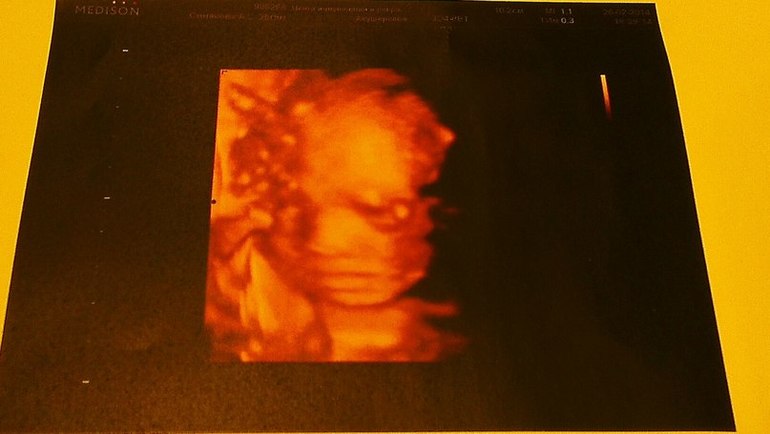

Пол малышаВчера были на узи. По совету двух подруг поехали в ЦИР (мне там очень понравилось!). Они смотрят сразу во всех форматах 2D-3D-4D - так здорово все видно! На прошлом узи, пролежав 20 минут, малышик так и не захотел показать пипильку -закрыл ее пятками и сдаваться не хотел. В этот раз наконец-то удалось подсмотреть! У нас маленькая Бусинка!! Такая красивищная, прям мимими

Папа был настроен на парнишку, но главное, что малышик по всем показателям хороший, все в норме, а еще мы длинююююющие ( мы с папой тоже высокие) - узист обещала модель

И такая скромница - дав все рассмотреть врачу, закрыла попу и писюльку ладошкой